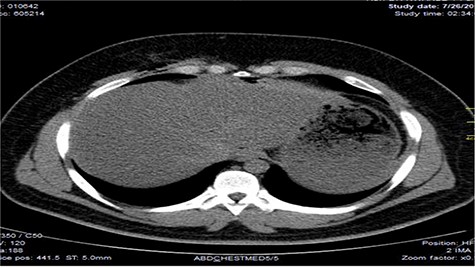

Chest X-ray was normal as shown in Fig. 1. Focused abdominal sonography for trauma (FAST) scan showed mild left perihepatic collection necessitating a thoracoabdominal computerized tomography (CT)-scan which showed external oblique muscle laceration with intermuscular air lucencies and grade 2 hepatic injury as shown in Figs 2–4. Other blood work-up were normal. No other injury was found on secondary survey. His wound was explored under local anaesthesia, primarily repaired, and he was discharged after 24 h of close observation.

Image shows lucent air densities tracking through the subcapsular haematoma in the left lobe of the liver anterior to the pylorus of the stomach.